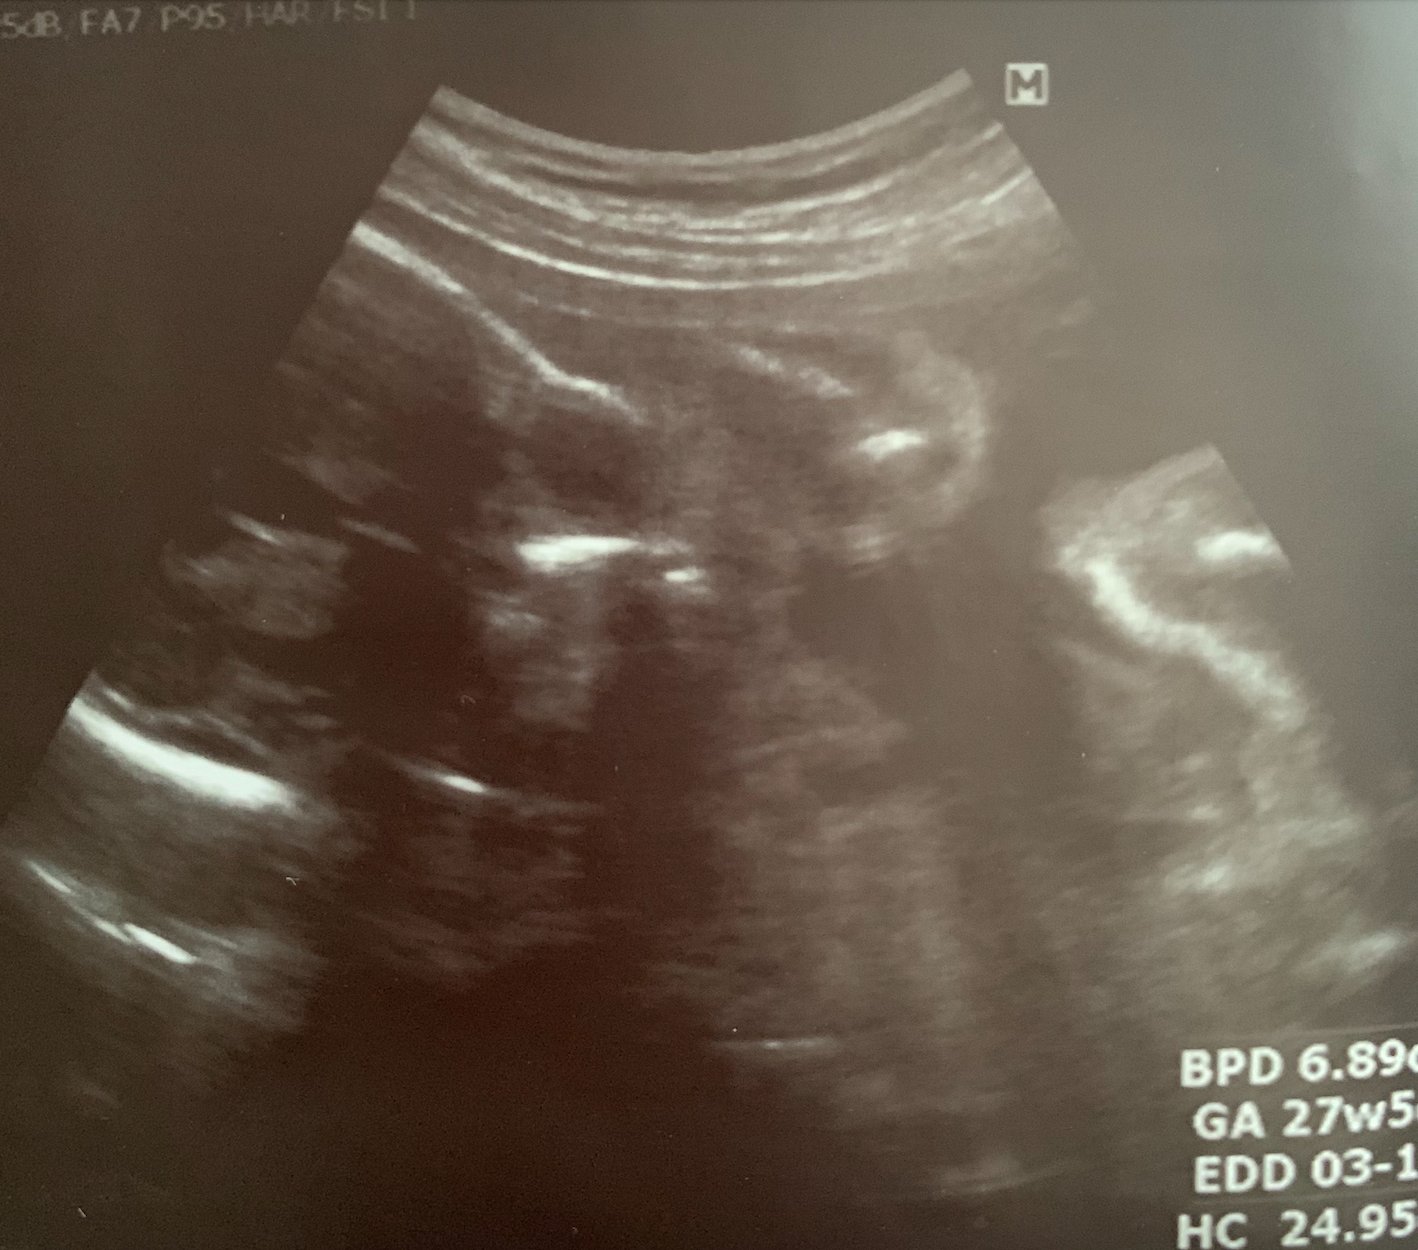

včera jsem byla na ultrazvuku miminka (27tt) a paní doktorka mi dala snímek, který jsem si bohužel prohlédla až doma. Miminko má na snímku velmi dlouhou lebku.

Může se jednat o kraniosynostózu nebo je takovýhle snímek běžný a je spíše nepovedený?

z této fotografie tvar lebky a případné patologie hodnotit nelze. K tomu jsou nutné jiné roviny řezu.